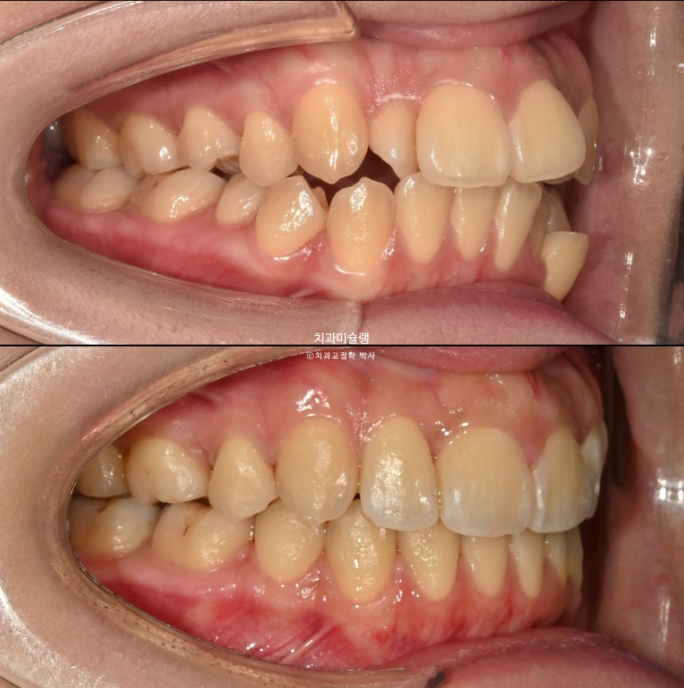

23.10~26.01

교합이 좋습니다.

스마일라인은 아랫입술과 평행하여 조화롭습니다.